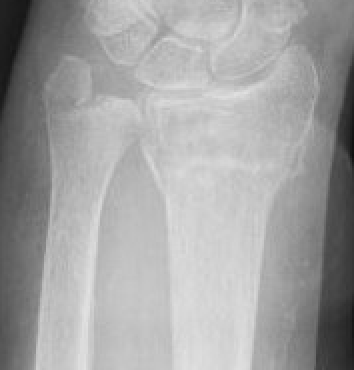

Classification ulna styloid fractures

| Type 1: Tip | Type 2: Base | Type 3: Proximal to styloid |

- RCT of 40 patients with distal radial fractures and base of ulna styloid fractures

- no instabililty, fixation v no fixation of ulna styloid process

- no difference between groups